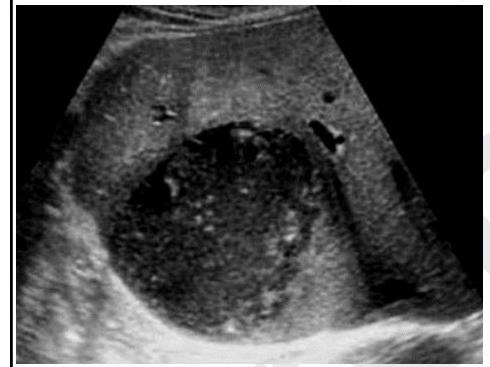

A 35-year-old patient with a history of dysentery for 6 weeks complains of pain in the right upper abdomen. On ultrasound, a hypoechoic hyperdense lesion is seen in the liver. Identify the condition based on the given image?

Explanation: ***Amoebic liver abscess*** - The patient's history of **dysentery** (amoebic colitis) 6 weeks prior strongly points to an amoebic infection, as *Entamoeba histolytica* can spread from the colon to the liver via the portal vein. - The ultrasound finding of a **hypoechoic lesion** in the liver is characteristic of an abscess, and in the context of recent dysentery, it is highly suggestive of an amoebic liver abscess. *Hydatid cyst* - Hydatid cysts are caused by *Echinococcus granulosus* and are typically seen in patients with a history of **sheep herding** or exposure to dogs. - Ultrasound findings often show **daughter cysts** or a "water lily" sign, which are not described here or evident in the image. *Hemangioma* - Hemangiomas are the **most common benign liver tumors** and are typically **hyperechoic** on ultrasound, unlike the hypoechoic lesion described. - They are usually **asymptomatic** and not associated with a history of dysentery or acute pain. *Pyogenic liver abscess* - While a pyogenic liver abscess can present as a hypoechoic lesion on ultrasound and cause pain, it is typically associated with **biliary tract infection**, diverticulitis, or other sources of bacterial infection, not usually dysentery alone. - Pyogenic abscesses are often **multiple** and frequently occur in the setting of conditions like cholangitis or appendicitis.